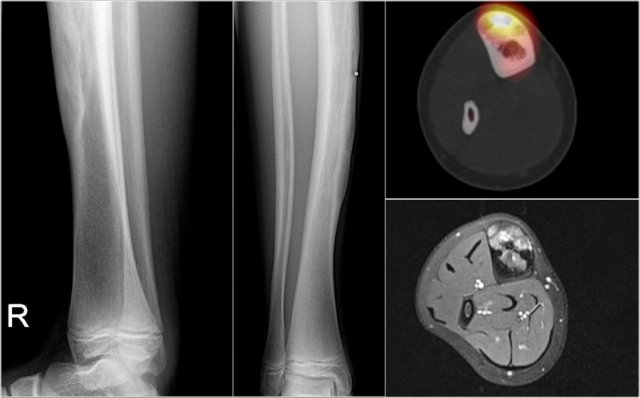

ABC (6) - atypical case

On the left two different patients with an intracortical or subperosteal osteolytic well-defined lesion in the tibia.

The lesion on the far left was thought to be an adamantinoma because of the localisation in the anterior tibial cortex.

At biopsy it proved to be an ABC.

The image on the right is an adamantinoma.

Continue with the additional examinations in this ABC.

Here the MR, bone scan and the sonogram of the same patient with ABC.

On the axial T2WI with fat saturation subtle sedimentation is seen.

The bone marrow is completely normal.